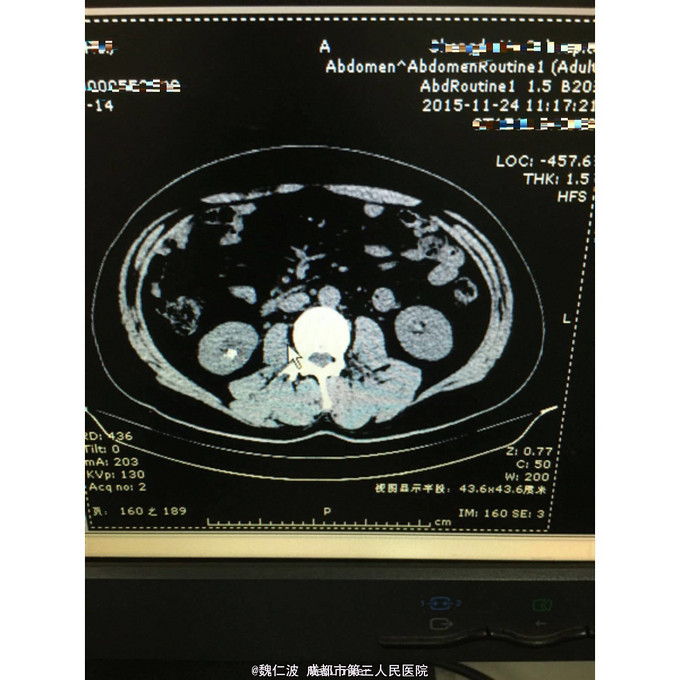

右侧输尿管结石碎石术后3月,发现右侧输尿管上段闭锁4天 3月前因右侧输尿管上端结石行输尿管软镜钬激光碎石,术后恢复可,但拍石稍差,1月后取支架管,术后2月复查右侧肾积水1厘米,3月复查积水5Cm,外院行右肾穿刺造瘘术,发现右侧输尿管上端闭锁,遂来我院。

右侧输尿管上端闭锁,右肾结石,右侧输尿管上端结石 经抗感染治疗后,行开放狭窄段切除,输尿管吻合术,安置F8输尿管支架管。